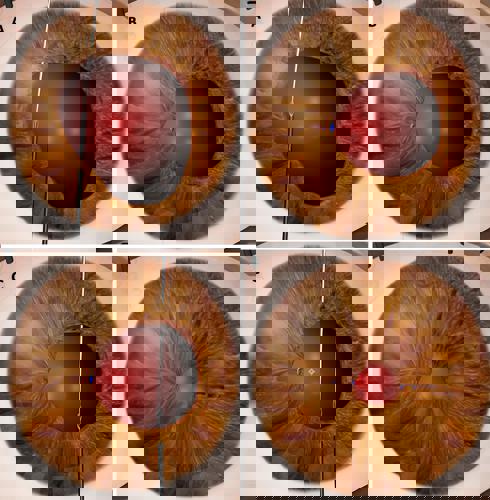

FIGURE: A) Single-pass, four-throw pupilloplasty bite is taken on one side of the pupil using 10-0 prolene suture on a long, thin needle. A 30-gauge needle is passed through a paracentesis and taken through the pupil on the other side. The first needle is railroaded into the 30-gauge needle to bring it out of the paracentesis; B) A loop is brought out and the leading end of the suture is cut and passed four times through the loop followed by pulling both ends apart to close the knot; C) A similar knot is taken on the other side; D) Multiple knots are taken until the pupil is small and centred on the patient-fixated, coaxially sighted corneal light reflex. A vitrector is used on a low cut rate and low vacuum to cut the pupil to adjust final size, shape, and centration.

A pinhole pupilloplasty is then performed by making multiple single-pass, four-throw pupilloplasties, preferably under viscoelastic. Vertical bites are usually preferred over horizontal, as hand movement is easier. A 10-0 prolene suture on a long, thin, curved needle is passed from the inferior limbus to take a bite of the iris about 1.0 mm from the margin. A 30-gauge needle is then passed through a paracentesis (ensuring the needle does not get caught in the incisional stroma by moving it gently side to side) and passed through the pupil on the other side, 1.0 mm from the limbus. The first needle is docked into the 30-gauge needle and railroaded out through the incision, followed by a suture loop brought out through the incision using a Kuglen hook. The cut end of the suture is then passed through the loop four times and the sutures on either side pulled outwards to internalise and tighten the knot. The sutures are cut close to the knot using a microscissor.

While passing the needles, care should be taken to be gentle and to avoid tearing the iris. Thin needles should be used, and excessive tug on the prolene suture avoided. A microforceps, passed through a side-port incision to hold the iris firmly, helps facilitate an atraumatic process. Additional passes are made on either side of the pupil as required (typically three on either side). Once the pupil is small, the final positioning and sizing of the PPP is done carefully with a vitrector using a low cut rate. Centration should ideally align with the preoperative mark made on the cornea. It is important to position the patient’s head without any tilt to avoid parallax error. An endodiathermy may also help in adjusting centration and sizing.